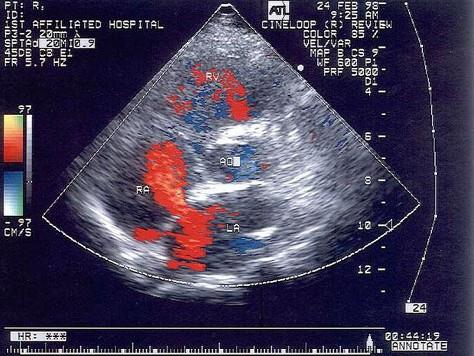

该病例最有可能诊断?(?)A.肺静脉畸形引流B.上腔静脉型房缺C.Ⅱ孔型房缺D.卵圆孔重开E.下腔静型房缺

选项 A.肺静脉畸形引流 B.上腔静脉型房缺 C.Ⅱ孔型房缺 D.卵圆孔重开 E.下腔静型房缺

答案 C